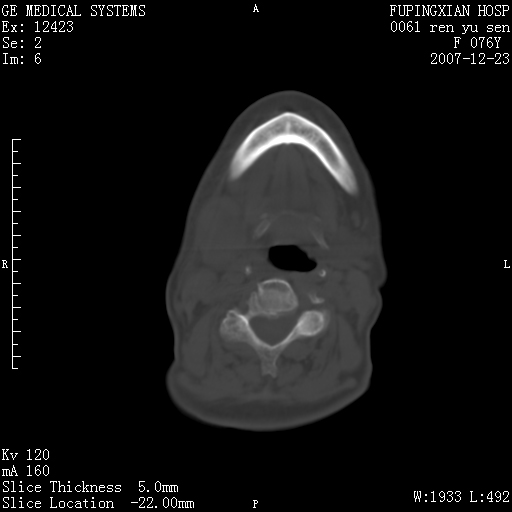

男性 76岁 下颌右侧磨牙区肿物数月, 约2.0*1.5cm大小波及颊舌侧,伴颌下淋巴结肿大。余(-)

右颈部颌下腺前可见一类圆形软组织密度影,密度不均,内见小片坏死区.颌下颈前可见两枚肿大淋巴结影.考虑淋巴结感染可能性大,建议增强扫描..

右侧第四磨牙缺失,局部牙槽骨质破坏,边界欠清晰,同侧颌下及竟不见多发肿大淋巴结显示。考虑肿瘤病变可能性大,感染待排